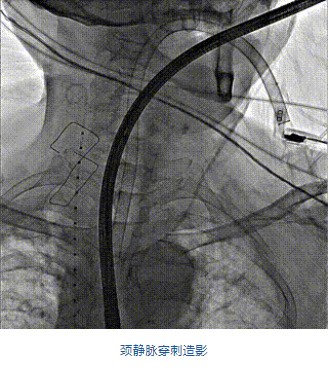

團(tuán)隊(duì)前期經(jīng)過多次討論,制定了周密的手術(shù)策略和預(yù)案。由于患者已是近九旬的超高齡老人,傳統(tǒng)外科開胸手術(shù)風(fēng)險極高,純介入經(jīng)血管三尖瓣替換能夠明顯減少創(chuàng)傷。術(shù)中陳茂及馮沅教授結(jié)合體表定位在造影指示下精準(zhǔn)穿刺右側(cè)頸靜脈并預(yù)置兩把血管縫合器。成功建立經(jīng)皮血管入路后在食道超聲和DSA的引導(dǎo)下順利完成人工瓣膜植入,術(shù)后超聲和造影顯示人工三尖瓣同軸性良好,瓣架固定牢靠,無反流和瓣周漏,平均跨瓣壓差降為1mmHg。術(shù)畢收緊預(yù)置的血管縫合器縫線完成止血,縫合效果滿意,在手術(shù)室即刻拔除氣管插管。

陳茂教授:LuX-Valve Plus經(jīng)血管三尖瓣置換系統(tǒng)可操作性強(qiáng),植入效果好,創(chuàng)傷很小,有望成為治療重度三尖瓣反流患者的“有力武器”。本次手術(shù)的成功驗(yàn)證了通過穿刺頸靜脈的純介入方式完成LuX-Valve Plus系統(tǒng)植入的可行性,也進(jìn)一步驗(yàn)證了通過該系統(tǒng)實(shí)施經(jīng)導(dǎo)管三尖瓣置換的安全性和有效性,期待在后期臨床研究開展中使更多的三尖瓣反流患者獲益。